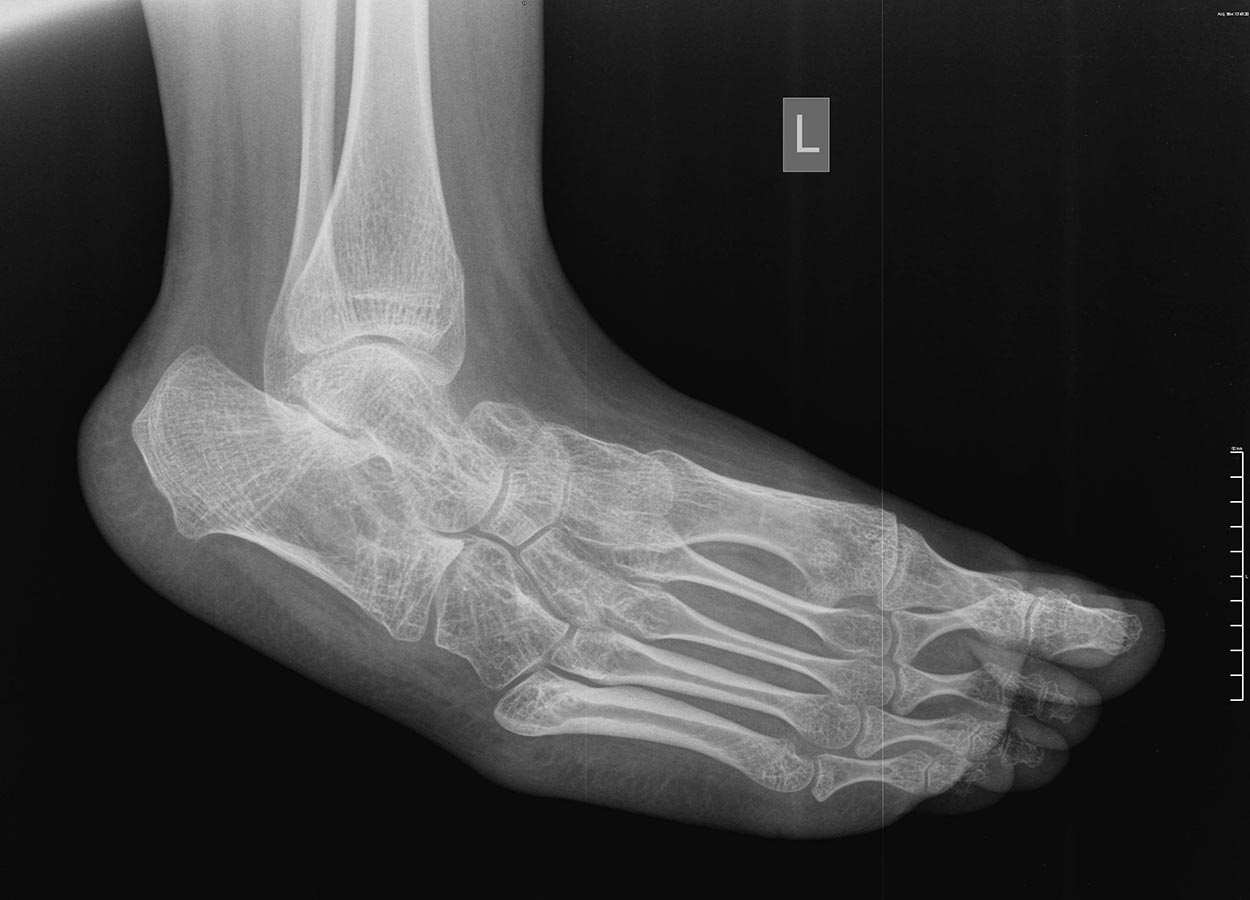

Девочка 15-и лет, страдает ДЦП

Уважаемый доктор Бахтамян, а что это за операция тенотомия икроножных мышц в подколенной ямке, наверное операция Страера имелось ввиду? "Хорошо разработана" и при этом девочка не ходит, а на фото тяжелая конская стопа. Так не бывает.

Откуда такая информация? Без рассечения дельтовидной связки не получить коррекцию варуса. Мягкотканного вмешательства достаточно не будет. На снимках выраженные нарушения формы костей стопы-и речи не идет о приемлемой биомеханике. Жуткая инконгруентность - хоть все сухожилия удлините, какой толк? Вызывает большие сомнения возможность почти полной пассивной коррекции деформации этих стоп. Но если она все-таки возможна - ничто не мешает выполнить ахиллопластику и трехсуставной артродез одномоментно без предварительного проведения гипсовой коррекции. Аппарат Илизарова для спастика - мучение для пациента и врача. Астрагалэктомия - зачем? Трехсуставной оставит голенстоп подвижным, после астрагалэктомии движений не будет. Да и просто не показана она здесь. Таранно-пяточный (подтаранный) сустав - не скакательный. Честно говоря, слышал только про скакательную связку стопы (пяточно-ладьевидная).

Снимок сделан в «произвольно-лежачем» положении, поэтому создаётся впечатление «грубой» деформации. В любом случае при патологии стопы при ДЦП функция важнее анатомии. Если Вы смогли вывести руками стопу до дорсифлексии, то на операционном столе вы выведите её ещё больше даже после Страйера. Варус тоже уйдёт (кстати, если Вы будете выводить стопу очень меденно, то, я думаю, варус ликвидируется даже при осмотре). У девочки диплегия и сгибательные контрактуры в коленных суставах, то есть, после удлиннения ахилловых сухожилий и капсулотомий большая вероятность развития crouch gait, это трагедия, которую трудно исправить. Лучше недокоррекция. В данном случае проблему нужно решать на уровне коленных и голеностопных суставов одномоментно. Разгибательные остеотомии н\3 бёдер + низведение надколенников + Страйер (эквинус не проблемма).

Леонид Сычевский 29 Апрель 2015, 00:22

Жалею, что поздно зашёл на этот топик. Вот смотрю я на фотографию - обычная,классическая стопа в эквиноварусной деформации при ДЦП. Смотрю Rg - снимки - обычные снимки эквиноварусной деформации при ДЦП, сделанные в том положении в котором они сделаны. Девочка ещё год назад ходила. Да это мечта любого ортопеда,занимающегося ДЦП. Какие артродезы и капсулотомии с пересадками. Поверьте мне Доктор Бахтамян, дадите наркоз, стопы выведутся, проверите Silverscold на операционном столе и , в зависимости от результата - удлиннение ахилла или Страйер. Я бы делал пересадку Ахилла кпереди и то что я написал выше, но это наши заморочки. Вам я рекомендую Страйера при сгибательных контрактурах в коленных суставах (лучше лёгкий эквинус чем crouch gait, тем более, что девочка уже выросла и рецидивов на будет). Операция 10 минут и Вы будете героем. Таких пациентов я прооперировал сотни. самая благодарная операция при ДЦП.

Уважаемый доктор Бхатамян, не делайте Rg-снимки стоп больным с ДЦП. Они не несут информации, не играют роль в принятии решения и вводят в заблуждение окружающих. Когда следующий раз придёт к Вам эта больная положите её на живот согните одну из ног в коленном суставе, положите свои ладони ей на стопы и медленно, очень медленно выведите стопы. Это, для Вас, будет доказательством того, что никаких «грубо-фиксированно-инконгруэтных» деформаций нет. Конечно, лечить больных с ДЦП не видя их трудно и глупо. Но, к счастью для нас, клинико-двигательные нарушения у больных с симметричной формой спастической диплегии проходят по определённому сценарию. У этой девочки 3 патерн этих нарушений (судя по фотографии и Вашим описаниям). Эквиноварусная деформация-сгибательная контрактура коленных суставов-сгибательная контрактура тазобедренных суставов (хотя Вы об этом не пишете, но она есть). Изолированное удлинение ахилловых сухожилий, тем более с капсулотомиями и прочее ПРОТИВОПОКАЗАНО. Исход - crouch gait. Это беда. Если дополнить релизом хамстрингов, исход передняя тазовая инклинация - это полбеды.Нужно делать релиз хамстрингов и релиз илиопсоас из внутритазового доступа (это принципиально). Но в 15-летнем возрасте релиз хамстрингов может не вывести коленные суставы до коррекции, поэтому я писал об остеотомиях. Если у Вас нет опыта лечения этих больных, то лучше не заморачиваться на всём этом, а сделать рецессиию гастрокнемиус (Страйер, Вульпеус, Бейкер, что лучше получается) и всё. Девочка опять будет ходить. Хотя плохо. Чтобы хорошо, запишите видео и вышлите, можно в личку. Я распишу операции. Ну,... моё мнение. Да, сделайте снимки тазобедренных суставов.